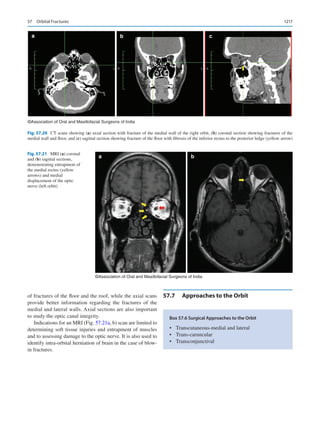

clindamycin with fluoroquinolone. Hematopoeitic growth

factors like granulocyte colony-stimulating factors or

granulocyte-­

macrophage colony-stimulating factors are